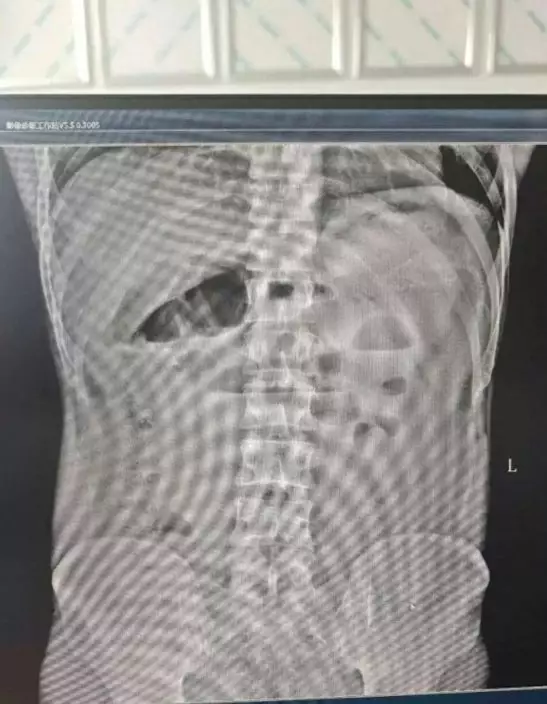

CT檢查發現腸穿孔 男子情況危急

經腹部CT檢查,醫生發現黃鱔已將男子的腸道鑽破造成「乙狀結腸穿孔」,而且男子全腹硬似木板、疼痛難忍,已出現「板狀腹」的危急症狀,這是致命的彌漫性腹膜炎,極有可能發展為感染性休克,情況相當危急。

黃鱔於湖南漢體內「遊走」情況危急。影片截圖